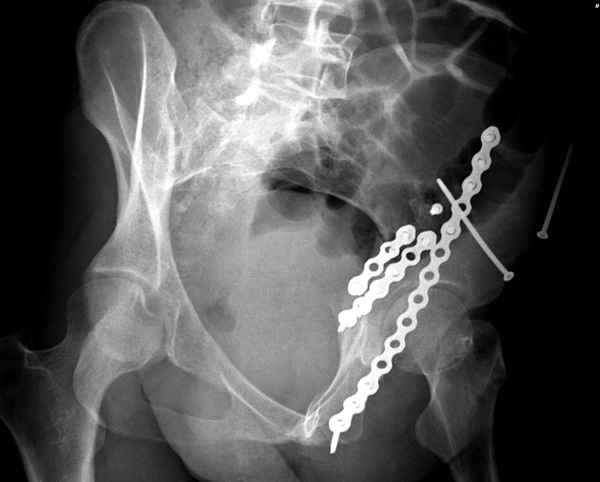

Вложение не в текстовом формате было извлечено&hellip;

Имя     : 3 Bothcolumn Judet 2.jpg

Тип     : image/jpeg

Размер  : 27444 байтов

Url     : http://weborto.net:8080/pipermail/ortho/attachments/20100506/5c268106/attachment-0015.jpg